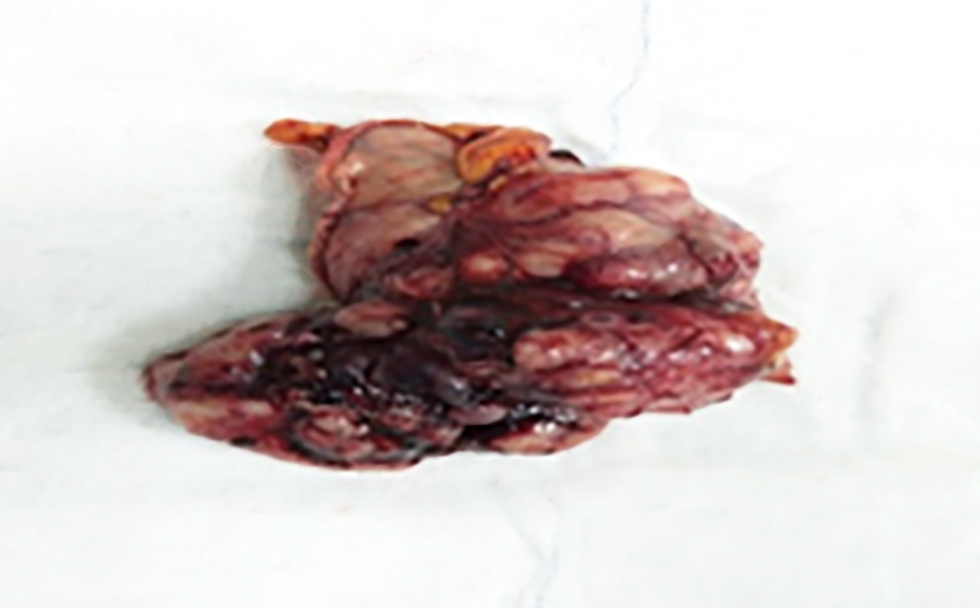

Macroscopic examination of the surgical specimen obtained after wedge resection for gastric GIST revealed a well-circumscribed, solid, submucosal mass with occasional haemorrhagic areas (fig. 3). This macroscopic appearance showed similar features in other GIST cases in our study.

Figure 3 - Surgical specimen after gastric wedge resection: Macroscopic view of the resected gastric GIST specimen showing a well-circumscribed, submucosal solid mass with areas of hemorrhage.